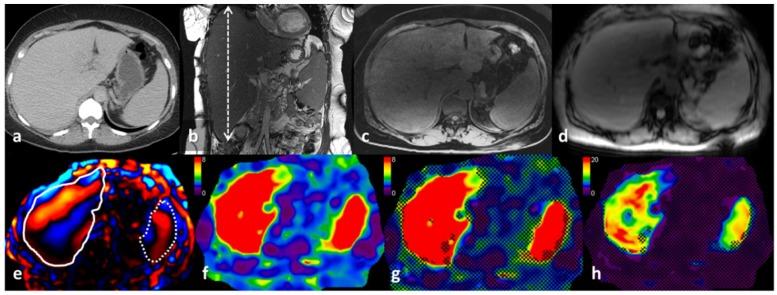

In this paper, we present our preliminary findings regarding magnetic resonance elastography (MRE) on the livers of 10 patients with systemic amyloidosis. Mean liver stiffness measurements (LSM) and spleen stiffness measurements (SSM) were obtained. Magnetic resonance imaging (MRI) images were analyzed for the distribution pattern of amyloid deposition. Pearson correlation analysis was performed in order to study the correlation between LSM, SSM, liver span, liver volume, spleen span, spleen volume, serum alkaline phosphatase (ALP), N-terminal pro b-type natriuretic peptide (NT pro BNP), and the kappa and lambda free light chains. An increase in mean LSM was seen in all patients. Pearson correlation analysis showed a statistically significant correlation between LSM and liver volume ( = 0.78, = 0.007) and kappa chain level ( = 0.65, = 0.04). Interestingly, LSM did not correlate significantly with SSM ( = 0.45, = 0.18), liver span ( = 0.57, = 0.08), or serum ALP ( = 0.60, = 0.07). However, LSM correlated significantly with serum ALP when corrected for liver volume (partial correlation, = 0.71, = 0.03) and NT pro BNP levels (partial correlation, = 0.68, = 0.04). MRI review revealed that amyloid deposition in the liver can be diffuse, lobar, or focal. MRE is useful for the evaluation of hepatic amyloidosis and shows increased stiffness in hepatic amyloidosis. MRE has the potential to be a non-invasive quantitative imaging marker for hepatic amyloidosis.

在本文中,我们展示了关于10例系统性淀粉样变性患者肝脏的磁共振弹性成像(MRE)的初步研究结果。获得了平均肝脏硬度测量值(LSM)和脾脏硬度测量值(SSM)。对磁共振成像(MRI)图像进行分析以观察淀粉样蛋白沉积的分布模式。进行Pearson相关性分析以研究LSM、SSM、肝径、肝脏体积、脾径、脾脏体积、血清碱性磷酸酶(ALP)、N末端B型利钠肽原(NT pro BNP)以及κ和λ游离轻链之间的相关性。所有患者的平均LSM均升高。Pearson相关性分析显示LSM与肝脏体积(r = 0.78,P = 0.007)和κ链水平(r = 0.65,P = 0.04)之间存在统计学显著相关性。有趣的是,LSM与SSM(r = 0.45,P = 0.18)、肝径(r = 0.57,P = 0.08)或血清ALP(r = 0.60,P = 0.07)无显著相关性。然而,在校正肝脏体积后LSM与血清ALP显著相关(偏相关性,r = 0.71,P = 0.03),与NT pro BNP水平也显著相关(偏相关性,r = 0.68, P = 0.04)。MRI检查显示肝脏中的淀粉样蛋白沉积可以是弥漫性、叶性或局灶性的。MRE有助于评估肝脏淀粉样变性,并且显示在肝脏淀粉样变性中硬度增加。MRE有可能成为肝脏淀粉样变性的一种非侵入性定量成像标志物。